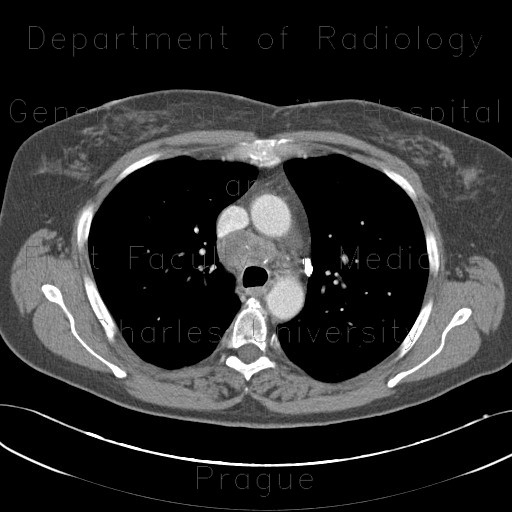

M/21

Incidental detected mass